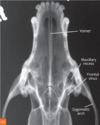

15

Q

A

fractured mandibula in oblique views

in the right mandibula view you can barely see the fracture due to superimposition of structures so capture both mandibula on their own image.